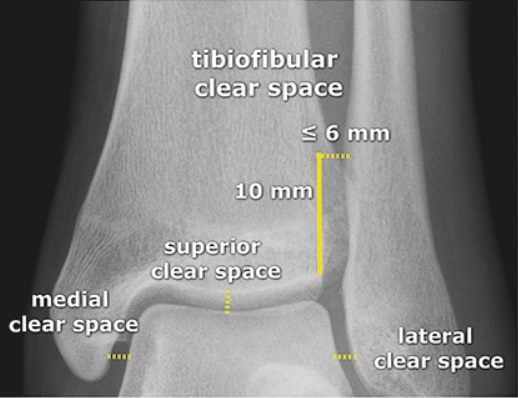

Klasické rtg projekce, ideálně se zatíženou DK, mohou odhalit zlomeninu nebo rozestup kostěné „vidlice“ (tibie a fibuly) při poruše syndesmózy. Je možné řídit se normativními hodnotami nazývanými jako tibiofibulární clear space a mediální clear space, které by měly být ≤ 6 mm (Obr 3). Vazivový aparát syndesmózy však na rtg přímo viditelný není a případný rozestup tibie a fibuly je pouze sekundárním ukazatelem s omezenou schopností odhalit subtilnější zranění. Z naší zkušenosti vyplývá, že tyto rozměry často ani hodnoceny nejsou a popis rtg snímků zraněného hlezna je většinou omezen na informaci o přítomnosti/nepřítomnosti defektu na skeletu. Vedle toho byla prokázána jen slabá korelace mezi měřením hodnot clear space  z rentgenových snímků a potvrzenými úrazy syndesmózy na MRI. (5) Naopak vyšetření syndesmózy na MRI prokazuje vysokou shodu mezi různými vyšetřujícími i vysokou senzitivitu a specificitu v porovnání s artroskopickými nálezy. Pomocí MRI však není možné provádět projekce se zatížením DK. Jako dobré řešení se jeví sonografie – pomocí diagnostického ultrazvuku můžeme zhodnotit klíčové komponenty syndesmózy a provádět dynamická vyšetření, tj. např. při zevní rotaci hlezna a vyšetření se zátěží DK. Důležité je i porovnání s druhostrannou končetinou. Diagnostickým ultrazvukem však ne vždy poznáme kostní zranění nebo osteochondrální léze, které mohou být přidruženy. Proto je vhodná kombinace s rtg. Můžeme však zaznamenat novotvorbu kostní hmoty ve smyslu přítomnosti osteofytů či heterotopických osifikací, tj. častých příčin dlouhodobé bolesti a dysfunkce regionu.

Obr. 3, Tibiofibulární clear space a mediální clear space zdravého kotníkuzdroj: https://www.startradiology.com/internships/general-surgery/ankle/x-ankle/; (kliknutím se zvětší)